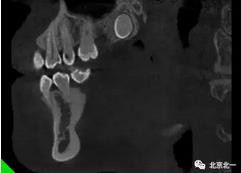

圖四:冠狀面截圖牙根位于唇側(cè),牙冠位于腭側(cè)。

圖五:矢狀位截圖可見牙冠截面。